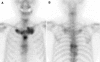

The concept of synovitis, acne, pustulosis, hyperostosis, osteitis (SAPHO) syndrome has been well clarified, after Chamot et al. suggested this peculiar disorder in 1987. The most commonly affected site in SAPHO syndrome is the anterior chest, followed by the spine. However, the clinical course and taxonomic concept of SAPHO spinal lesions are poorly understood. This study was performed to analyze: (1) the detailed clinical course of spinal lesions in SAPHO syndrome, and (2) the relationship between SAPHO syndrome with spinal lesions and seronegative spondyloarthropathy. Thirteen patients with spondylitis in SAPHO syndrome were analyzed. The features of spinal lesions were a chronic onset with a slight inflammatory reaction, and slowly progressing non-marginal syndesmophytes at multi spinal levels, besides the coexistence of specific skin lesions. SAPHO syndrome, especially spinal lesions related to palmoplantar pustulosis, can be recognized as a subtype of seronegative spondyloarthropathy.